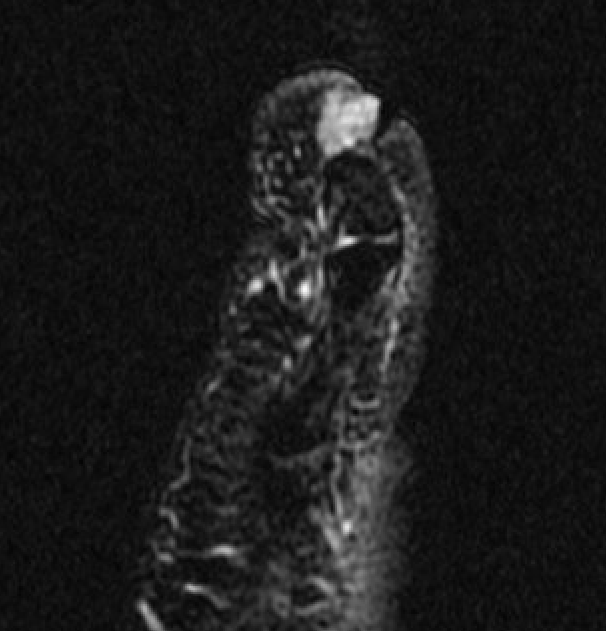

Subungal glomus tumor distal phalanx 5th toe

MRI

Subungal glomus tumor 5th toe